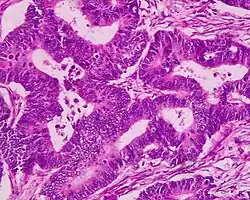

| Villous adenoma | 15%[16] to 40%[15] | Over 75% villous[14] |

| |

The villous subdivision is associated with the highest malignant potential because they generally have the largest surface area. (This is because the villi are projections into the lumen and hence have a bigger surface area.) However, villous adenomas are no more likely than tubular or tubulovillous adenomas to become cancerous if their sizes are all the same.[18]

Micrograph of a villous adenoma. These polyps are considered to have a high risk of malignant transformation. H&E stain. -